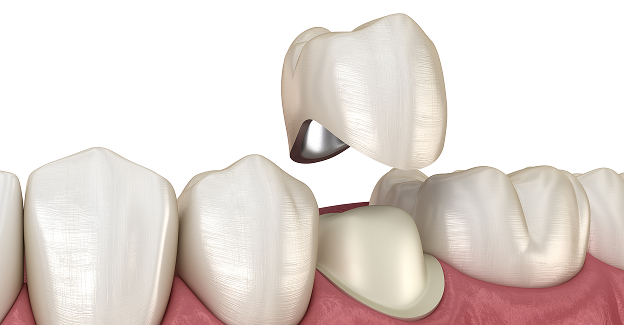

STEP 04

신경치료04

치아파절 방지를 위한

크라운 보철 씌우기

골드 크라운

치아와의 적합성이 뛰어나며, 씹는 힘이 강한 어금니에 적합합니다.

금속 재료이지만 생체 친화적이며, 잇몸 자극이 적습니다.

• 높은 강도

• 생체 친화적

지르코니아 크라운

강도가 높은 세라믹 소재로, 자연치아와 유사한 색상과

내구성을 가지며 치아와의 밀착력도 우수합니다.

• 뛰어난 심미성

• 자연스러움